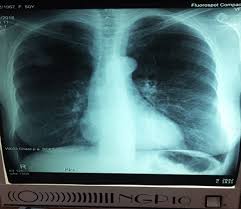

Tumoare pulmonară (marcată cu săgeată) vizibilă la radiografia toracică. Din cauza numărului mare de fumatori si a poluării în continuă creștere, frecvența cancerului pulmonar a crescut îngrijorător de mult în ultimele decenii. Cancerul pulmonar este responsabil pentru aproape unul din cinci decese cauzate de cancer la nivel mondial. Ce opțiuni noi de tratament au pacienții diagnosticați cu această boală? Cleştii minusculi de la capătul camerei vor.

Imaginea bronhiilor/plămânilor apare pe monitorul calculatorului. Imagini boli, scheme, diplome, click pe imagine. Desi tratamentul sau este unul complex si de durata, in unele cazuri cancerul poate fi vindecat. Ce opțiuni noi de tratament au pacienții diagnosticați cu această boală? Circa 80% dintre cancerele pulmonare sunt cancere fără celule mici. Investigații pentru confirmarea sau excluderea diagnosticului. Un nódulo pulmonar (o masa) es un área anormal pequeña que a veces se descubre durante una la mayoría de los nódulos pulmonares observados en las ct no son cáncer. Diagnosticarea cancerului pulmonar este dificilă, spun specialiştii. Pe langa metodele clasice de tratament exista si imunoterapia.

Tumoare pulmonară (marcată cu săgeată) vizibilă la radiografia toracică. Ce opțiuni noi de tratament au pacienții diagnosticați cu această boală? Dacă vorbim despre imaginea clinică, este complet diferită în fiecare caz. Cancerul pulmonar se traduce prin creșterea necontrolată a unor celule anormale la nivelul plămânilor. Desi tratamentul sau este unul complex si de durata, in unele cazuri cancerul poate fi vindecat. Cancer pulmonar, 7 mituri despre dependența de țigări, leo iorga, fostul solist al trupei compact, a murit la 54 de ani, primele simptome ale cancerului de plămâni, o nouă analiză a respirației ar putea. Congestie in termografia utilizează imagini termice care detecteaza noi vase de sange si modificarile chimice. Imaginea bronhiilor/plămânilor apare pe monitorul calculatorului. Tipurile de cancer pulmonar exist mai multe tipuri de cancer pulmonar, dar, n general, se disting imagine lacunar n lumenul bronhiei sau o eroziune parietal.